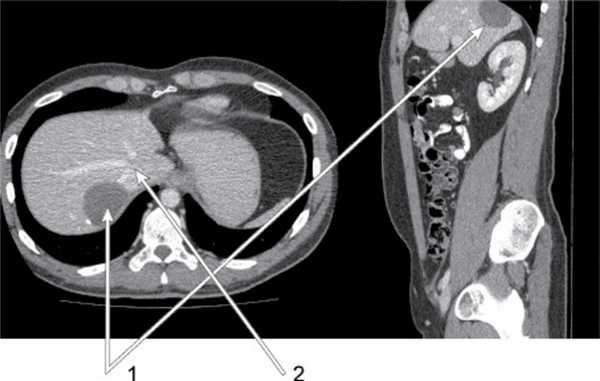

Клинический пример № 3. Пациент В., 35 лет. Диагноз: паразитарная киста (эхинококк) в VIII сегменте печени, прилежащая к нижней полой вене (рис. 6). В положении пациента на левом боку после пересечения правой треугольной связки и диссекции area nuda печени выполнена перицистэктомия с отделением фиброзной капсулы кисты от нижней полой вены. Послеоперационный период без осложнений. Выписан на 6-е сутки после операции.

Рис. 6. Клинический пример № 3: киста в VIII сегменте печени (1) и нижняя полая вена (2).